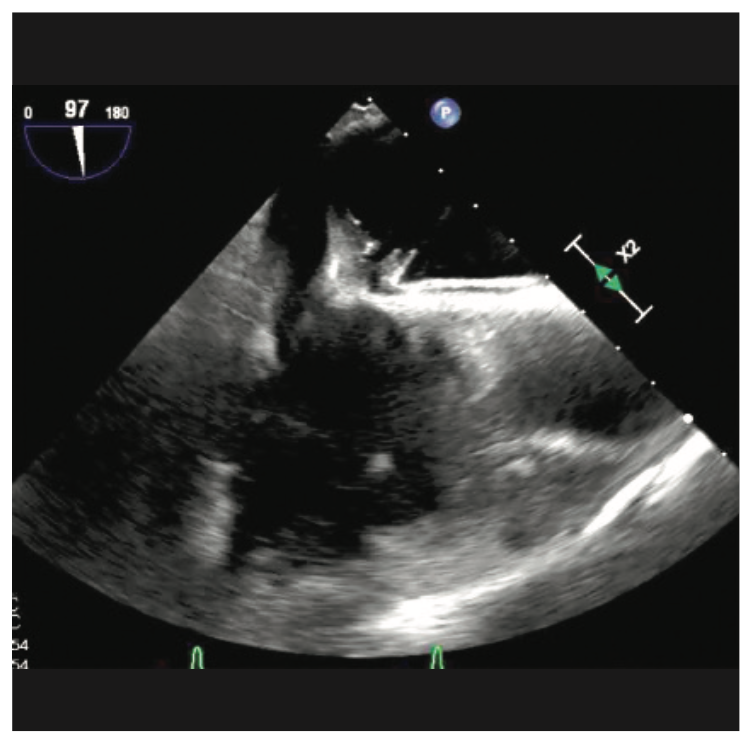

An 80-year-old female with a history of heart failure with reduced ejection fraction, hypertension, and chronic kidney disease presented with worsening dyspnea and fatigue for 6 months despite being on optimal guideline-directed medical therapy. An echocardiogram revealed an ejection fraction of 30%-35% and severe mitral valve regurgitation. A coronary angiogram revealed no significant obstructive coronary artery disease. After discussing different options with the patient, it was opted to proceed with mitral valve repair using MitraClip (Abbott Vascular).

Crossing the interatrial septum was challenging. Although we were able to cross the interatrial septum with a transseptal needle, advancing the sheath across the fossa ovalis was difficult. Several maneuvers such as rotating and redirecting the sheath were not successful. Pre-dilation of the septum with 5 mm x 40 mm balloon did not allow for insertion of the MitraClip guide across the interatrial septum. At this point, we elected to use the balloon-assisted tracking (BAT) technique. Using a 7 mm x 40 mm balloon that was inflated to 10 atmospheres (atm) at the tip of the guiding catheter, we were able to advance the sheath through interatrial septum (Figures/Videos 1-3). Subsequently, a G4 XTW MitraClip was successfully deployed in the central position. A post procedure transesophageal echocardiogram showed mild mitral regurgitation.